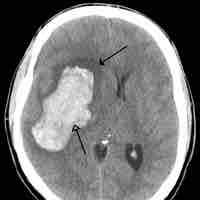

Brain Tumors

A brain tumor is a pathological abnormal growth of cells in the brain.